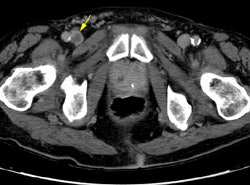

The example below demonstrates a pulmonary embolism in the left lower lobe pulmonary artery (Yellow arrows). Due to venous enhancement, clot can be seen within the right common femoral vein (Yellow arrow). The peripheral venous enhancement on this image obtained 3 minutes following intiation of the contrast infusion was approximately 90HU. The clot had an HU measurement of 44. (Click to view larger images if desired)